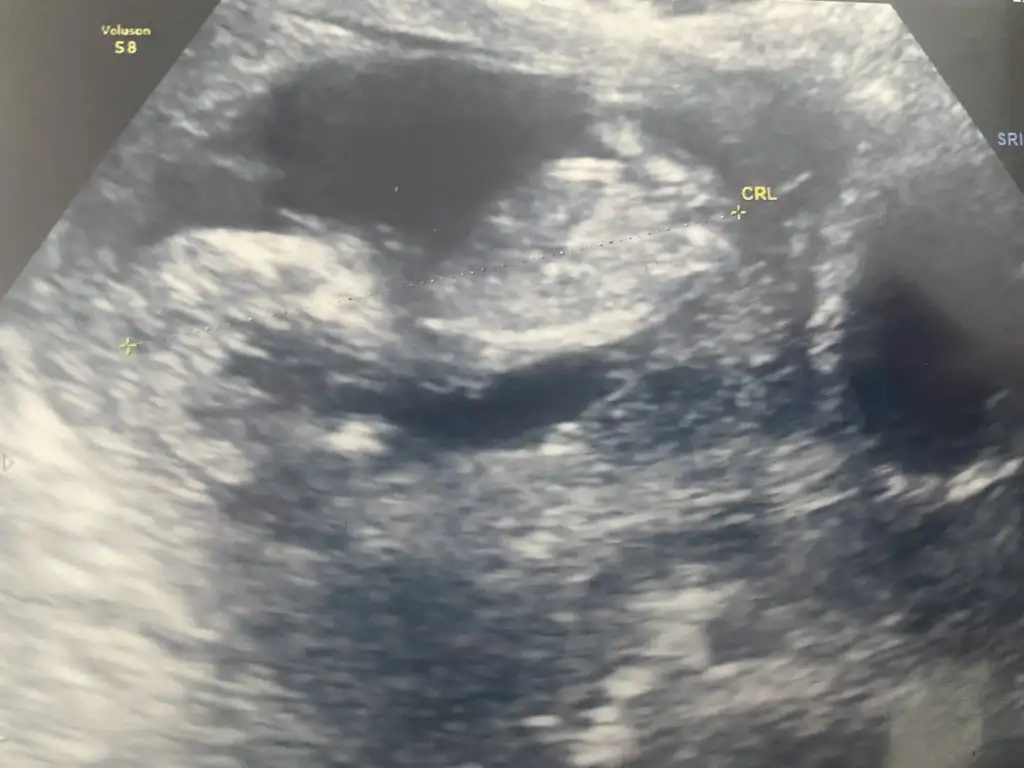

5 ve 14. haftaya kadar olan ultrasyon fotolarınızı paylaşın. Vajinadan mı yoksa karından mı çekildiğini ve kaç haftalık olduğunu da mutlaka belirtin.

Not: Tahmin yaptığım anneler cinsiyet öğrendikten sonra lütfen bana geri dönüş yapın![]()

Evet normal dedi gayet. Niye kierkek gibi kuzum7+5 de CRL 1.38 e doktor normal dedi mi?

evet kuzum kese içinde bebeğin olması şartCanım ultrasonda bebek göründükten sonra mi tahminde bulunabiliyorsun

15 şuan, görüntüler 13 haftalıktan göstermedi bebiş o gün :)canım kaç haftalık?